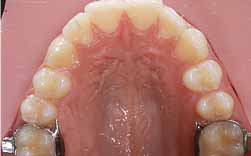

A perda de um molar de leite deve ser de imediato compensada com um dispositivo mantedor do espaço.

Quando a perda já se verifica e o exames demonstram a existência de falta de espaço para a erupção dever-se-à recorrer a um dispositivo apropriado para a recuperação do mesmo.